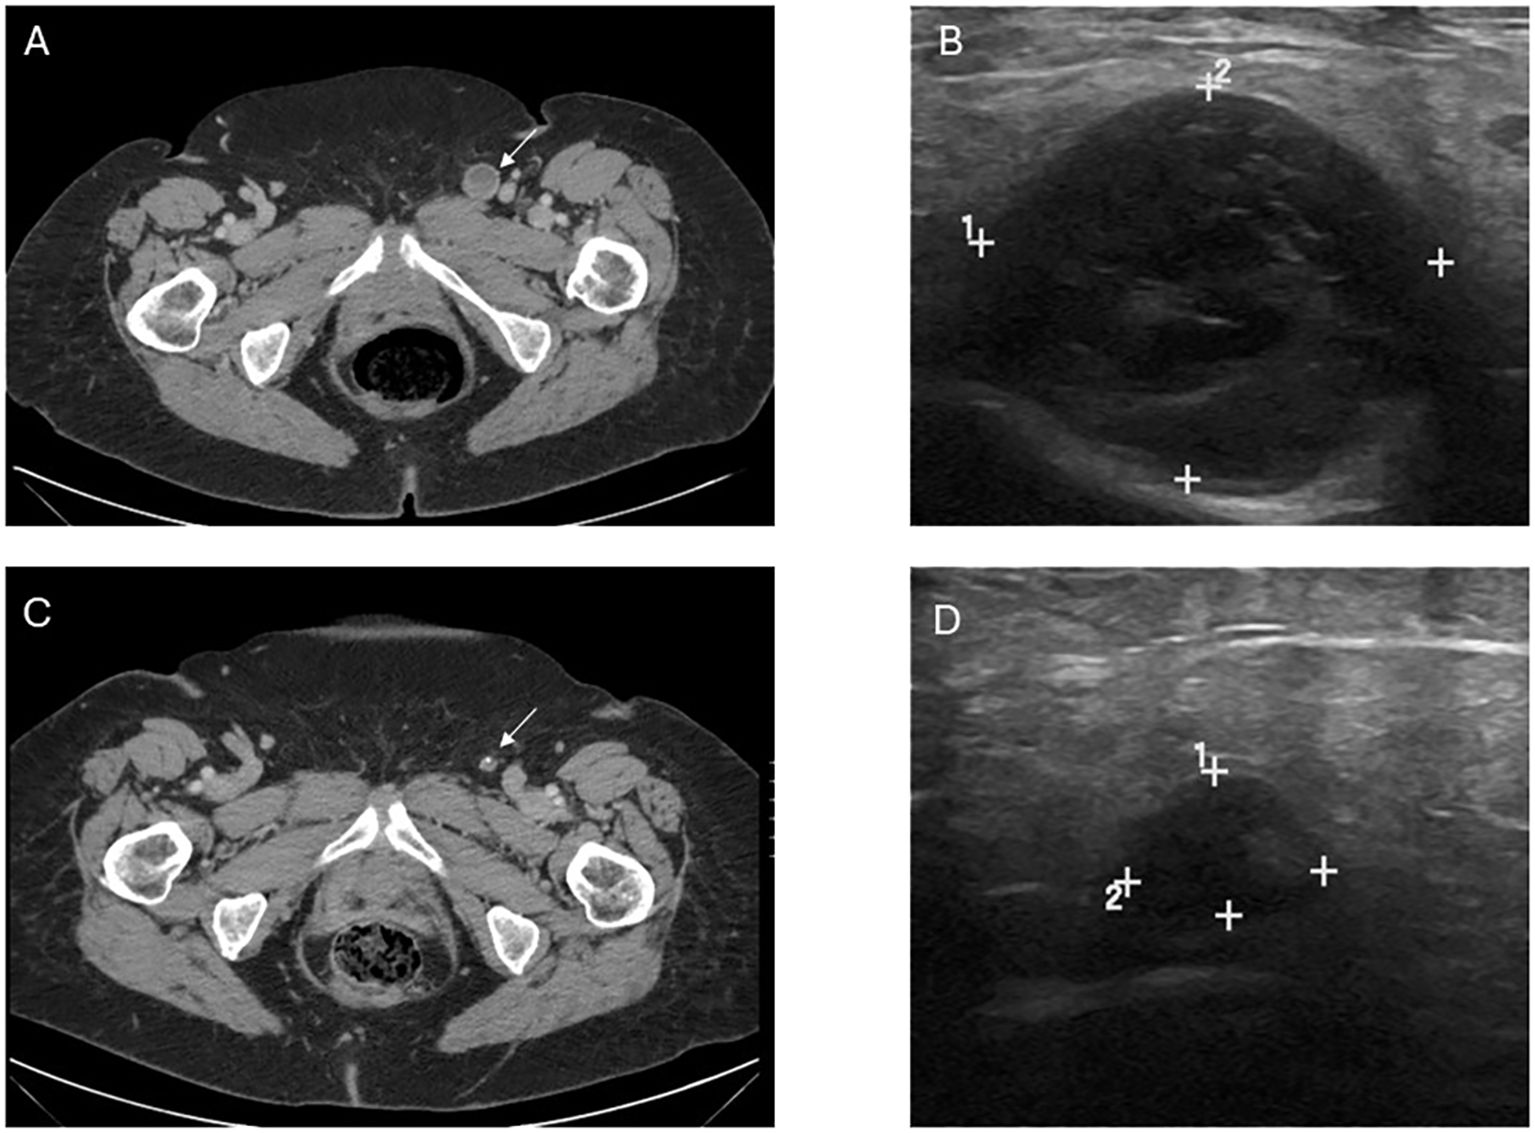

She was started on immunotherapy with immune checkpoint inhibition (ICI) with nivolumab that was complicated by development of autoimmune hepatitis after its first dose in January 2019. This was treated with a steroid taper. She was offered pelvic exenteration but ultimately opted against such extensive surgery. In the following months, she developed worsening vaginal bleeding, causing significant lifestyle limitations, and she underwent palliative resection with R1 resection margins. Months later, her lymph nodes were noted to be enlarged and nivolumab therapy was restarted with palliative intent to maximize quality of life as patient was not amenable to extensive pelvic exenteration. She initially had partial response to the treatment as defined by the Immune Response Evaluation Criteria in Solid Tumors (iRECIST), without signs of hepatitis recurrence. However, a repeat computed tomography (CT) scan in 2021 showed progression of her disease, with a left inguinal lymph node noted to have increased from 0.8 cm to 2.0 cm in size. She therefore underwent a fine needle aspiration (FNA) confirming the diagnosis of metastatic malignant melanoma. Options for locoregional control including both surgical lymphadenectomy and intralesional therapy were discussed with the patient. She strongly desired to avoid the morbidity of surgery and was subsequently started on intralesional injections of T-VEC to the metastatic lymph node. She received T-VEC injections every 3 weeks over a 12-month time period with a total of 17 treatments. The initial dose was administered as 1 mL of 10^6 plaque-forming units (PFU). Subsequent doses were all full strength at 10^8 PFU with volume adjusted based on ultrasound measurements of the size of lymph node (ranged from 0.5–2 mL). Concomitantly, she was switched to pembrolizumab therapy so she could receive her ICI and T-VEC administrations on the same day. Repeat FNA of the treated lymph nodes after the completion of her T-VEC treatment showed no signs of residual metastatic disease in the lymph node. She continued in surveillance with clinical examinations, initially with frequent nodal ultrasound to supplement her axial imaging. Maintenance Pembrolizumab therapy was continued at 6-week intervals thereafter for 10 months. Of note, biopsy of the inguinal lymph node was negative though ctDNA was low positive at 0.06 mean tumor molecules/mL. Her latest CT scan of the chest, abdomen, and pelvis 2.5 years after cessation of T-VEC treatment and 19 months after discontinuing ICI did not show any signs of metastatic disease (Figure 1). A timeline of her clinical course is reported in Figure 2.

Figure 1. Image findings before and after T-VEC treatment. (A) Computed tomography (CT) demonstrating the abnormal lymph node consistent with metastatic melanoma prior to treatment. (B) Pretreatment ultrasound showing the enlarged, hypoechoic lymph node in the left inguinal region corresponding with the CT finding and measuring 2.3 x 2.1 x 2.7 cm. (C) Post-treatment CT demonstrating decrease in size and near resolution of lymph node, in which fine needle aspiration was unable to retrieve any viable melanoma. (D) Post-treatment US with significant decrease in size, measuring 1.2 x 0.5 x 0.7 cm though with some persistent abnormal morphology. Post-treatment size and morphology remained stable on axial and sonographic imaging after treatment discontinuation.